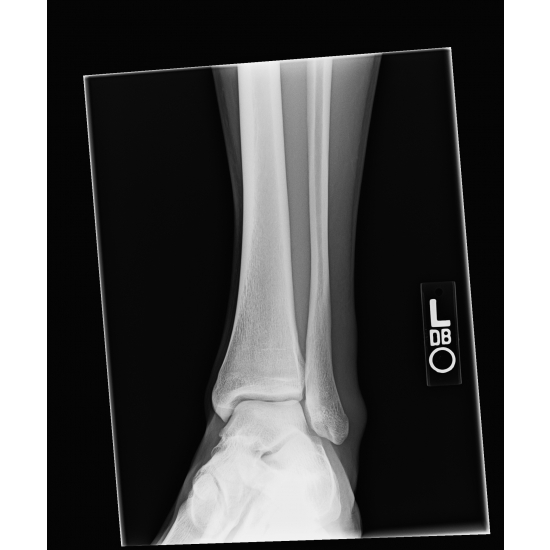

| Not Just Another Ankle Sprain - Page #3 | |||